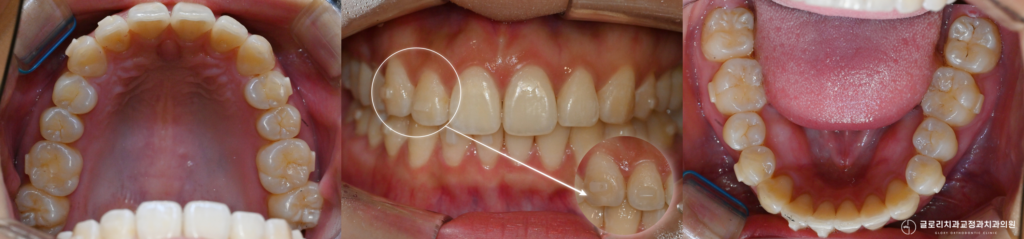

특히 윗앞니가 벌어지면 웃을 때 신경이 쓰이고 사진 찍을 때도 입을 다물게 되는 등 일상에서 불편함을 느끼시는 경우가 많습니다.

이 기간 동안 보정장치 착용이 소홀해지면 다음처럼 재발로 인한 치아 벌어짐으로 치아 재교정이 필요해지는데 한 번 틀어진 치아는 통제가 어려운 상황이 될 수 있습니다.

어태치먼트는 치아 표면에 부착하는 작은 돌기 형태의 장치입니다.

치아와 유사한 색상의 레진 소재로 만들어져 눈에 잘 띄지 않으면서도 중요한 역할을 수행합니다.

재교정 후에는 벌어졌던 앞니 사이 공간이 닫히며 다시 가지런해진 치열을 확인할 수 있습니다.